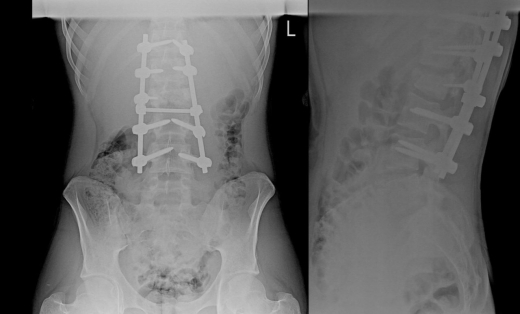

16-летний подросток не мог пошевелить ногами после того, как на него упало бревно. Воронежские медики провели ребёнку срочную ночную операцию по установке титановых пластин. Спустя месяцы реабилитации он снова ходит. Подробностями этой истории поделились в группе регионального министерства здравоохранения во «ВКонтакте» в понедельник, 26 января. Подросток получил травму в июле прошлого года, когда помогал на стройке отцу – участнику СВО. На ребёнка упало тяжелое бревно. Как итог: переломы позвонков и ребер, ушибы легких и пневмоторакс. После травмы парень даже не мог пошевелить ногами. Подростка отвезли в районную больницу, а оттуда – в воронежскую больницу скорой помощи №1. Счёт шёл на часы, поэтому оперировали ночью. Как пояснил хирург Александр Максимов, медики провели сразу два сложнейших вмешательства – декомпрессию нервных структур и фиксацию пяти позвонков титановой конструкцией. Такой подход позволил избежать длительного постельного режима и дал шанс на раннюю реабилитацию. Когда состояние подростка стабилизировалось, его перевели в областную детскую клиническую больницу №2. Там началась реабилитация под руководством заведующего отделением Дмитрия Клименко. Массажи, лечебная физкультура, занятия на специальных тренажерах – два курса реабилитации завершились только в декабре. Сейчас молодой человек ходит и живет полной жизнью. Врачи продолжают наблюдать за его состоянием.